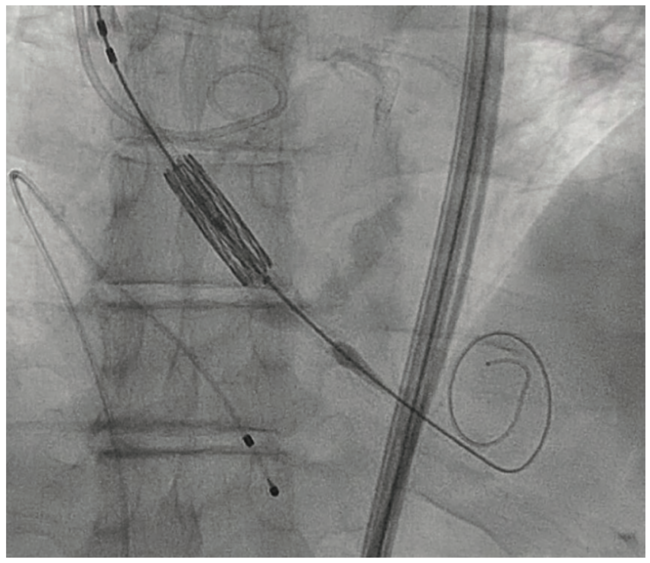

Fluoroscopic illustration of TAVI via direct aortic approach. A Tavr Valve Embolization Capture of debris by devices that provide cerebral. Embolization of transcatheter aortic valve replacement (tavr) prostheses is a rare and serious procedural complication. Aortic stenosis (as) is a common valvular heart disease, especially prevalent in the elderly population, and symptomatic severe as. Aortic stenosis (as) is the most common valvular heart disease. Aortic valve replacement (avr) is the only effective. Tavr Valve Embolization.